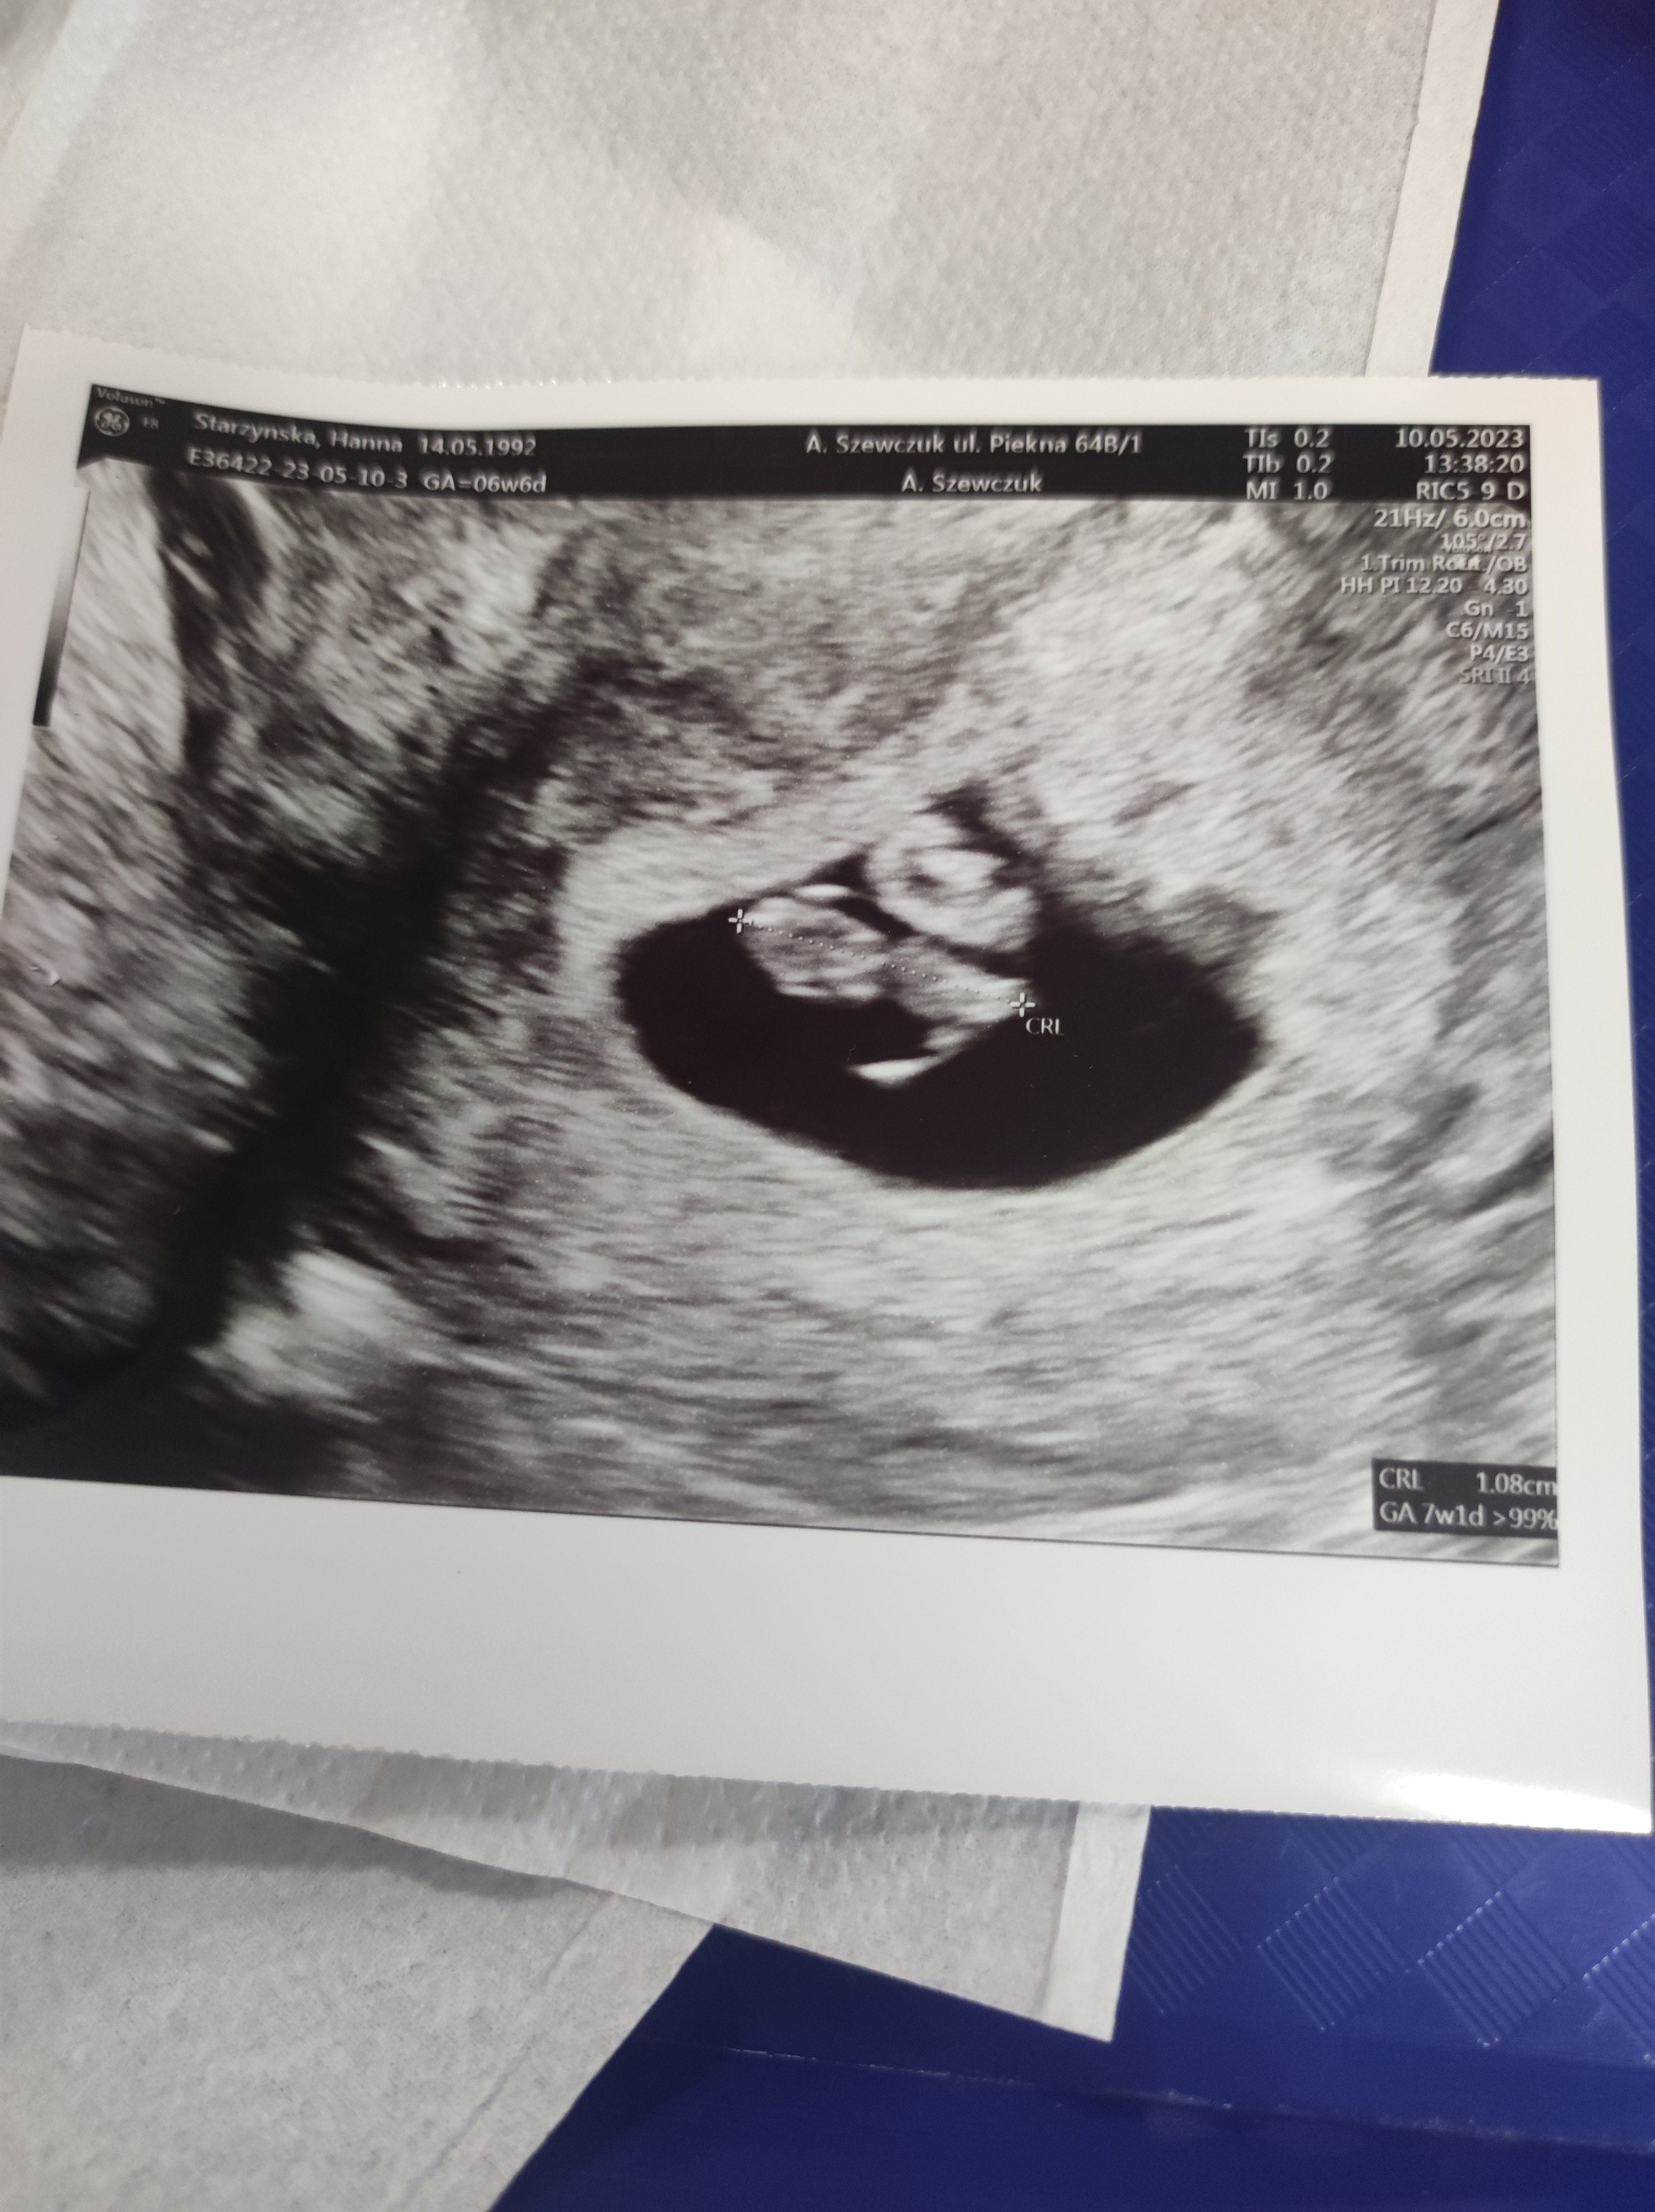

Ja już po wizycie.Powiem Wam 4 ciąża a pietra miałam jak przy pierwszej😜 Widać narazie pęcherzyk. Kolejna wizyta za 2 tyg. I komplet badań do zrobienia.🙊. Kartę ciąży już dostaliśmy😊. Pozdrawiam i spokojnego weekendu

IMG_20230513_111542.jpg